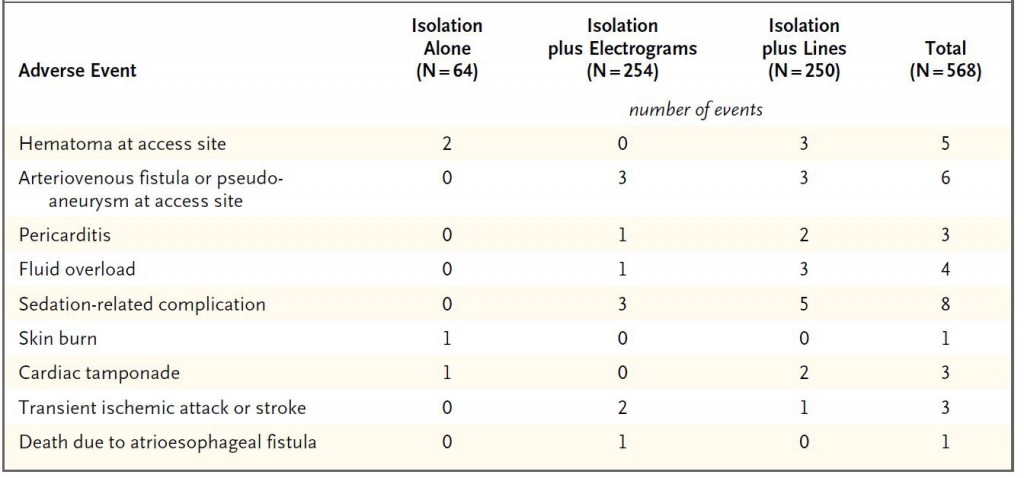

ひとつ目はSTAR-AF Ⅱ Trialです。その後のアブレーション方針に非常に大きな影響を与えました。この試験結果はアブレーターにとってある意味ショッキングなものでした。良かれと思って頑張って行ってきた追加アブレーションの効果が否定されてしまったのです。しかも、合併症のテーブルを見ますと(表)、左房食道瘻に伴う死亡例がCFAE追加例で生じています!アブレーションに関連する数ある合併症の中で最も致死的なものが左房食道瘻です。これは左房後面に接している食道が焼灼の熱によって障害されて生じる合併症です。頻度は非常に希ですが、一度生じると致死的です。1例でも生じてほしくない重大合併症がNEJMに掲載されるような大規模試験に参加する施設で生じている事実は重く受け止めなければならないでしょう。もちろんこの試験の結果だけで全てのCFAEアブレーションや線状焼灼の意義が否定された訳ではありませんが、追加アブレーションにはリスクが伴うことを術者はしっかり胸に刻んでおかねばなりません。

表:手技に伴う合併症。